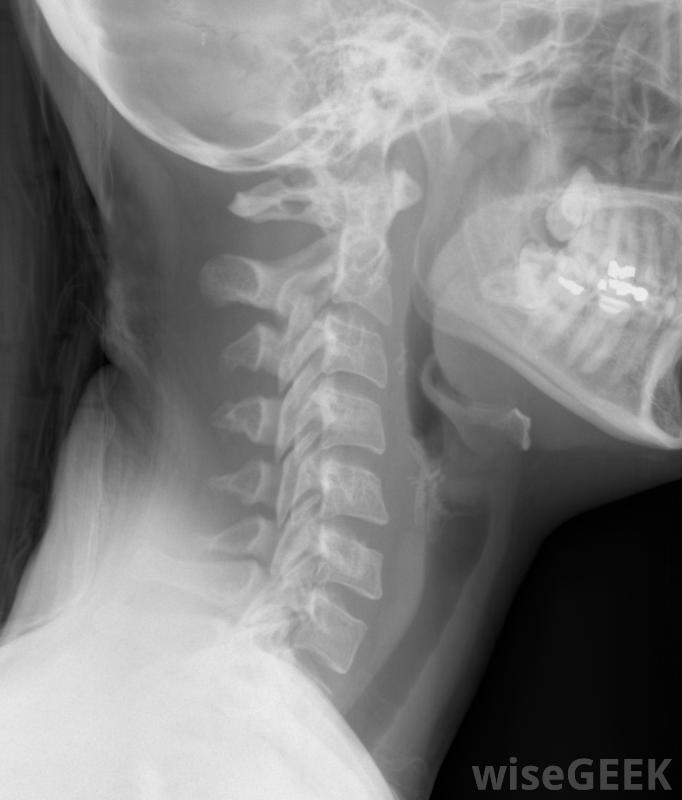

寰枢椎半脱位是指影响脊柱顶部的情况。半脱位是脱位的另一个术语,寰枢椎指的是上两个颈椎。当发生脱位或不稳定时,它可能是轻微到严重的,由许多不同的因素引起。在最坏的情况下,松驰的脊柱有可能压迫脊髓造成永久性损伤或死亡,但有些人的病情较轻,只需几周的治疗就可以痊愈颈部X光片,包括椎骨。寰枢椎半脱位的原因不是单一的。当人们遭受严重的颈部创伤时,有时会发生这种情况成人患这种病是由于关节炎,特别是类风湿性关节炎。它可能在任何影响呼吸道的疾病后突然发生,如肺炎,也可能在脊柱手术后出现。先天性疾病导致肌肉或结缔组织张力差,如马凡氏症或唐氏综合征也与脊柱疾病有关,在其他情况下,这种情况作为先天性缺陷单独出现在儿童身上。

对于轻度寰枢椎半脱位,医生的最终目标是稳定患者;当病情可疑时,通常可以通过各种扫描很容易地诊断出来。这些扫描包括计算机断层扫描(CT)、x光片和磁共振成像(MRI),内科医生转向治疗。

寰枢椎半脱位可通过MRI扫描进行诊断。治疗寰枢椎半脱位最有效的措施是外科手术。脊柱融合术可防止错位,虽然它也可能轻微地减少活动范围。根据病因或严重程度,可能需要一次以上的手术。如果半脱位造成脊髓压迫,前景并不总是乐观的。脊髓损伤,尤其是重大损伤,可能并非所有情况下都可修复,尽管在某些情况下神经外科医生或骨科医生能够成功地恢复部分或全部功能。